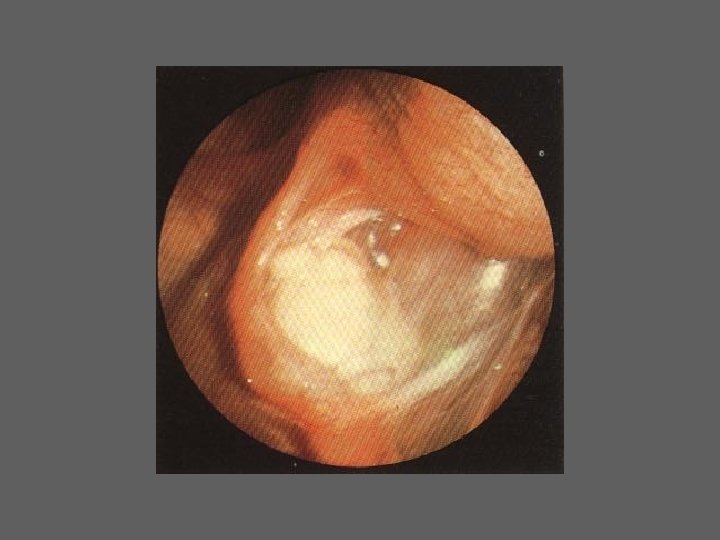

HISTEROSCOPIA - INDICAÇÕES Todas a situações em que se julgue vantajosa uma visualização completa da cavidade uterina, em particular: – Metrorragias – Dismenorreia adquirida – Infertilidade – Abortamentos de repetição e parto pré-termo – HSG anormal – DIU “perdido” – GIFT e ZIFT – Tratamento cirúrgico da patologia intracavitária: ● pólipos, miomas, septos, sinéquias, recessões endometriais ● baixos custos, reduzida morbilidade

HISTEROSCOPIA - MATERIAL CO 2 – Insuflador – Metrorragias max. 100 ml /min p < 100 mm Hg liquido (soro glicosado, dextrano, etc. ) – Fonte de luz fria – Histeroscópio (3, 5, 7 mm) – rígido ou flexível – Bainha e instrumentos cirúrgicos (pinça de biopsia, tesoura, etc.